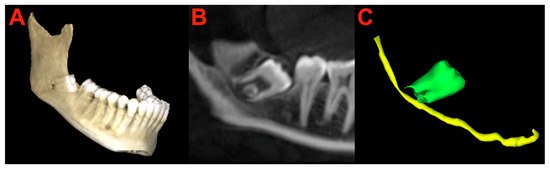

2.6. Segmentation and Preparation

2.7. Surgery